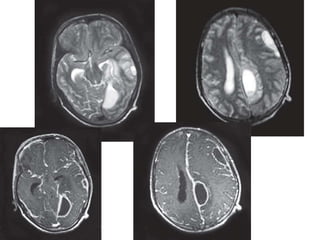

Axial T2W MR images (A, B) showing dilated

Virchow-Robin spaces in a bilateral and

symmetric manner involving the basal ganglia.

Also seen are round hyperintense lesion in

periventricular region and the left cerebellar

hemisphere representing cryptococcomas (C,

D)—

Cryptococcosis in an immunocompromised

patient